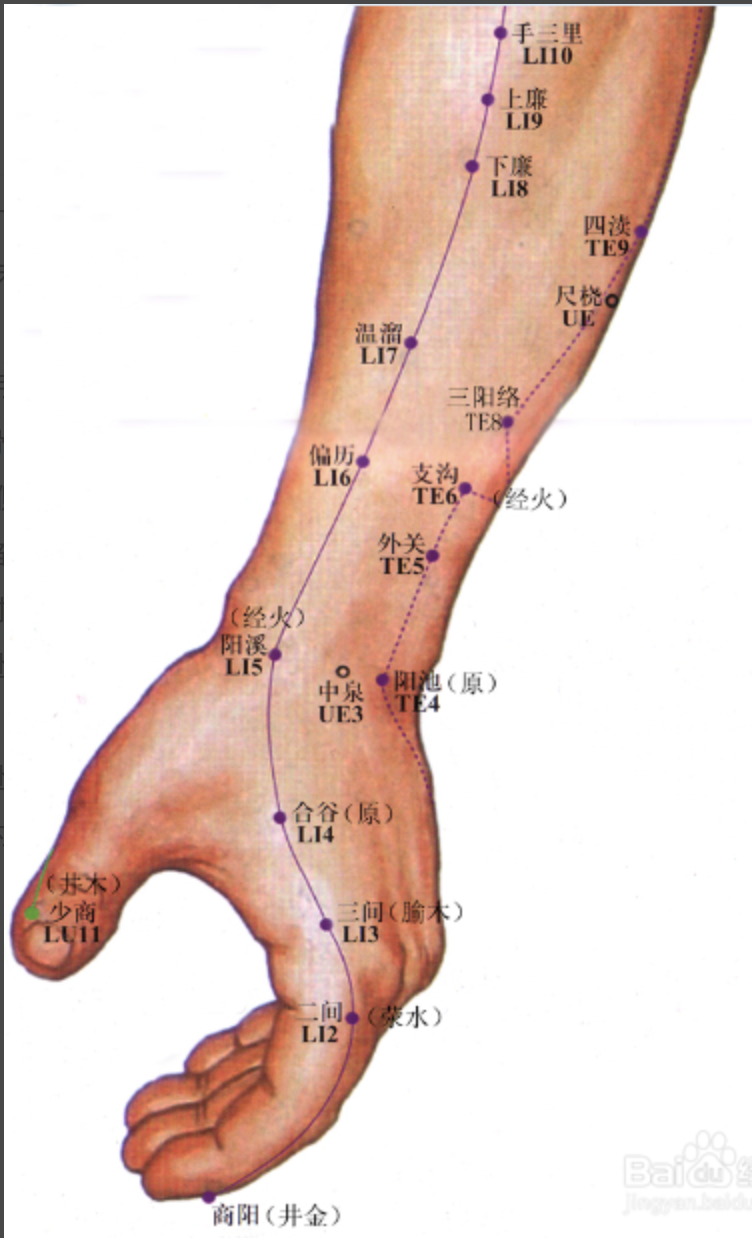

【(二)手阳明大肠经(图10-20-1)】

2、歌诀 手阳明穴起商阳,二间三间合谷藏,阳溪偏历历温溜,下廉上廉三里长,曲池肘髎(liáo)迎五里,臂臑(nào)肩髎(liáo)巨骨起,天鼎浮突接禾髎(liáo),终以迎香二十止。

3、经脉循行 起于食指末端(商阳),沿食指外(桡)侧向上,通过一、二掌骨之间(合谷)向上进入两筋(拇长伸肌腱与拇短伸肌腱)之间的凹陷处,沿前臂前方,至肘部外侧,再沿上臂外侧前缘,上走肩端(肩髃(yú)),沿肩峰前缘向上出于颈椎(大椎),再向下入缺盆(锁骨上窝)部,联络肺脏,通过横膈,属于大肠。

从食指末端起始(商阳),沿食指桡侧缘(二间、三间),出第一、二掌骨间(合谷)、进入两筋(拇长伸肌腱和拇短伸肌腱)之间(阳溪),沿前臂桡侧(偏历、温溜、下廉、上廉、手三里),进入肘外侧(曲池、肘髎),经上臂外侧前边(手五里、臂臑),上肩,出肩峰部前边(肩髃、巨骨,会秉风),向上交会颈部(会大椎),下入缺盆(锁骨上窝),络于肺,通过横膈,属于大肠。

合谷

【定位】 在手背,第1、2掌骨间,当第 2 掌骨桡侧的中心点(图 10-20-2)。

简便取穴:以一手的拇指指骨关节横纹,放在另一手拇、食指之间的指蹼缘上,当拇指尖下是穴。

【主治】 头痛,目赤肿痛,鼻衄,齿痛,牙关紧闭,口眼歪斜,耳聋,痄腮,咽喉肿痛,热病无汗,多汗,腹痛,便秘,经闭,滞产。

【配伍】 配太阳治头痛,配太冲治目赤肿痛,配迎香治鼻疾,配少商治咽喉肿痛,配三阴交治经闭、滞产,配地仓、颊车治口眼歪斜。

【刺灸法】 直刺 0.5 ~ 1 寸。

【附注】 (1)手阳明经所过为“原”。(2)《神应经》:孕妇不宜针。别名:虎口。

曲池

【定位】 在肘横纹外侧端,屈肘成直角,当尺泽与肱骨外上髁(kē)连线中点。

【主治】 热病,上肢不遂,咽喉肿痛,齿痛,目赤痛,瘰疬,瘾疹,手臂肿痛,腹痛吐泻,高血压,癫狂。

【配伍】 配血海、足三里治瘾疹,配手三里治上肢不遂,配太冲、大椎治高血压。

【刺灸法】 直刺 1 ~ 1.5 寸。

【附注】 (1)手阳明经所入为“合”。(2)参考资料:据报道,在犬阑尾壁内直接注射β-链球菌合金黄色葡萄球菌的混合菌液以引起实验性阑尾炎,用强刺激手法针刺“曲池”合“阑尾”穴,证明对实验性阑尾炎有肯定的治疗作用。